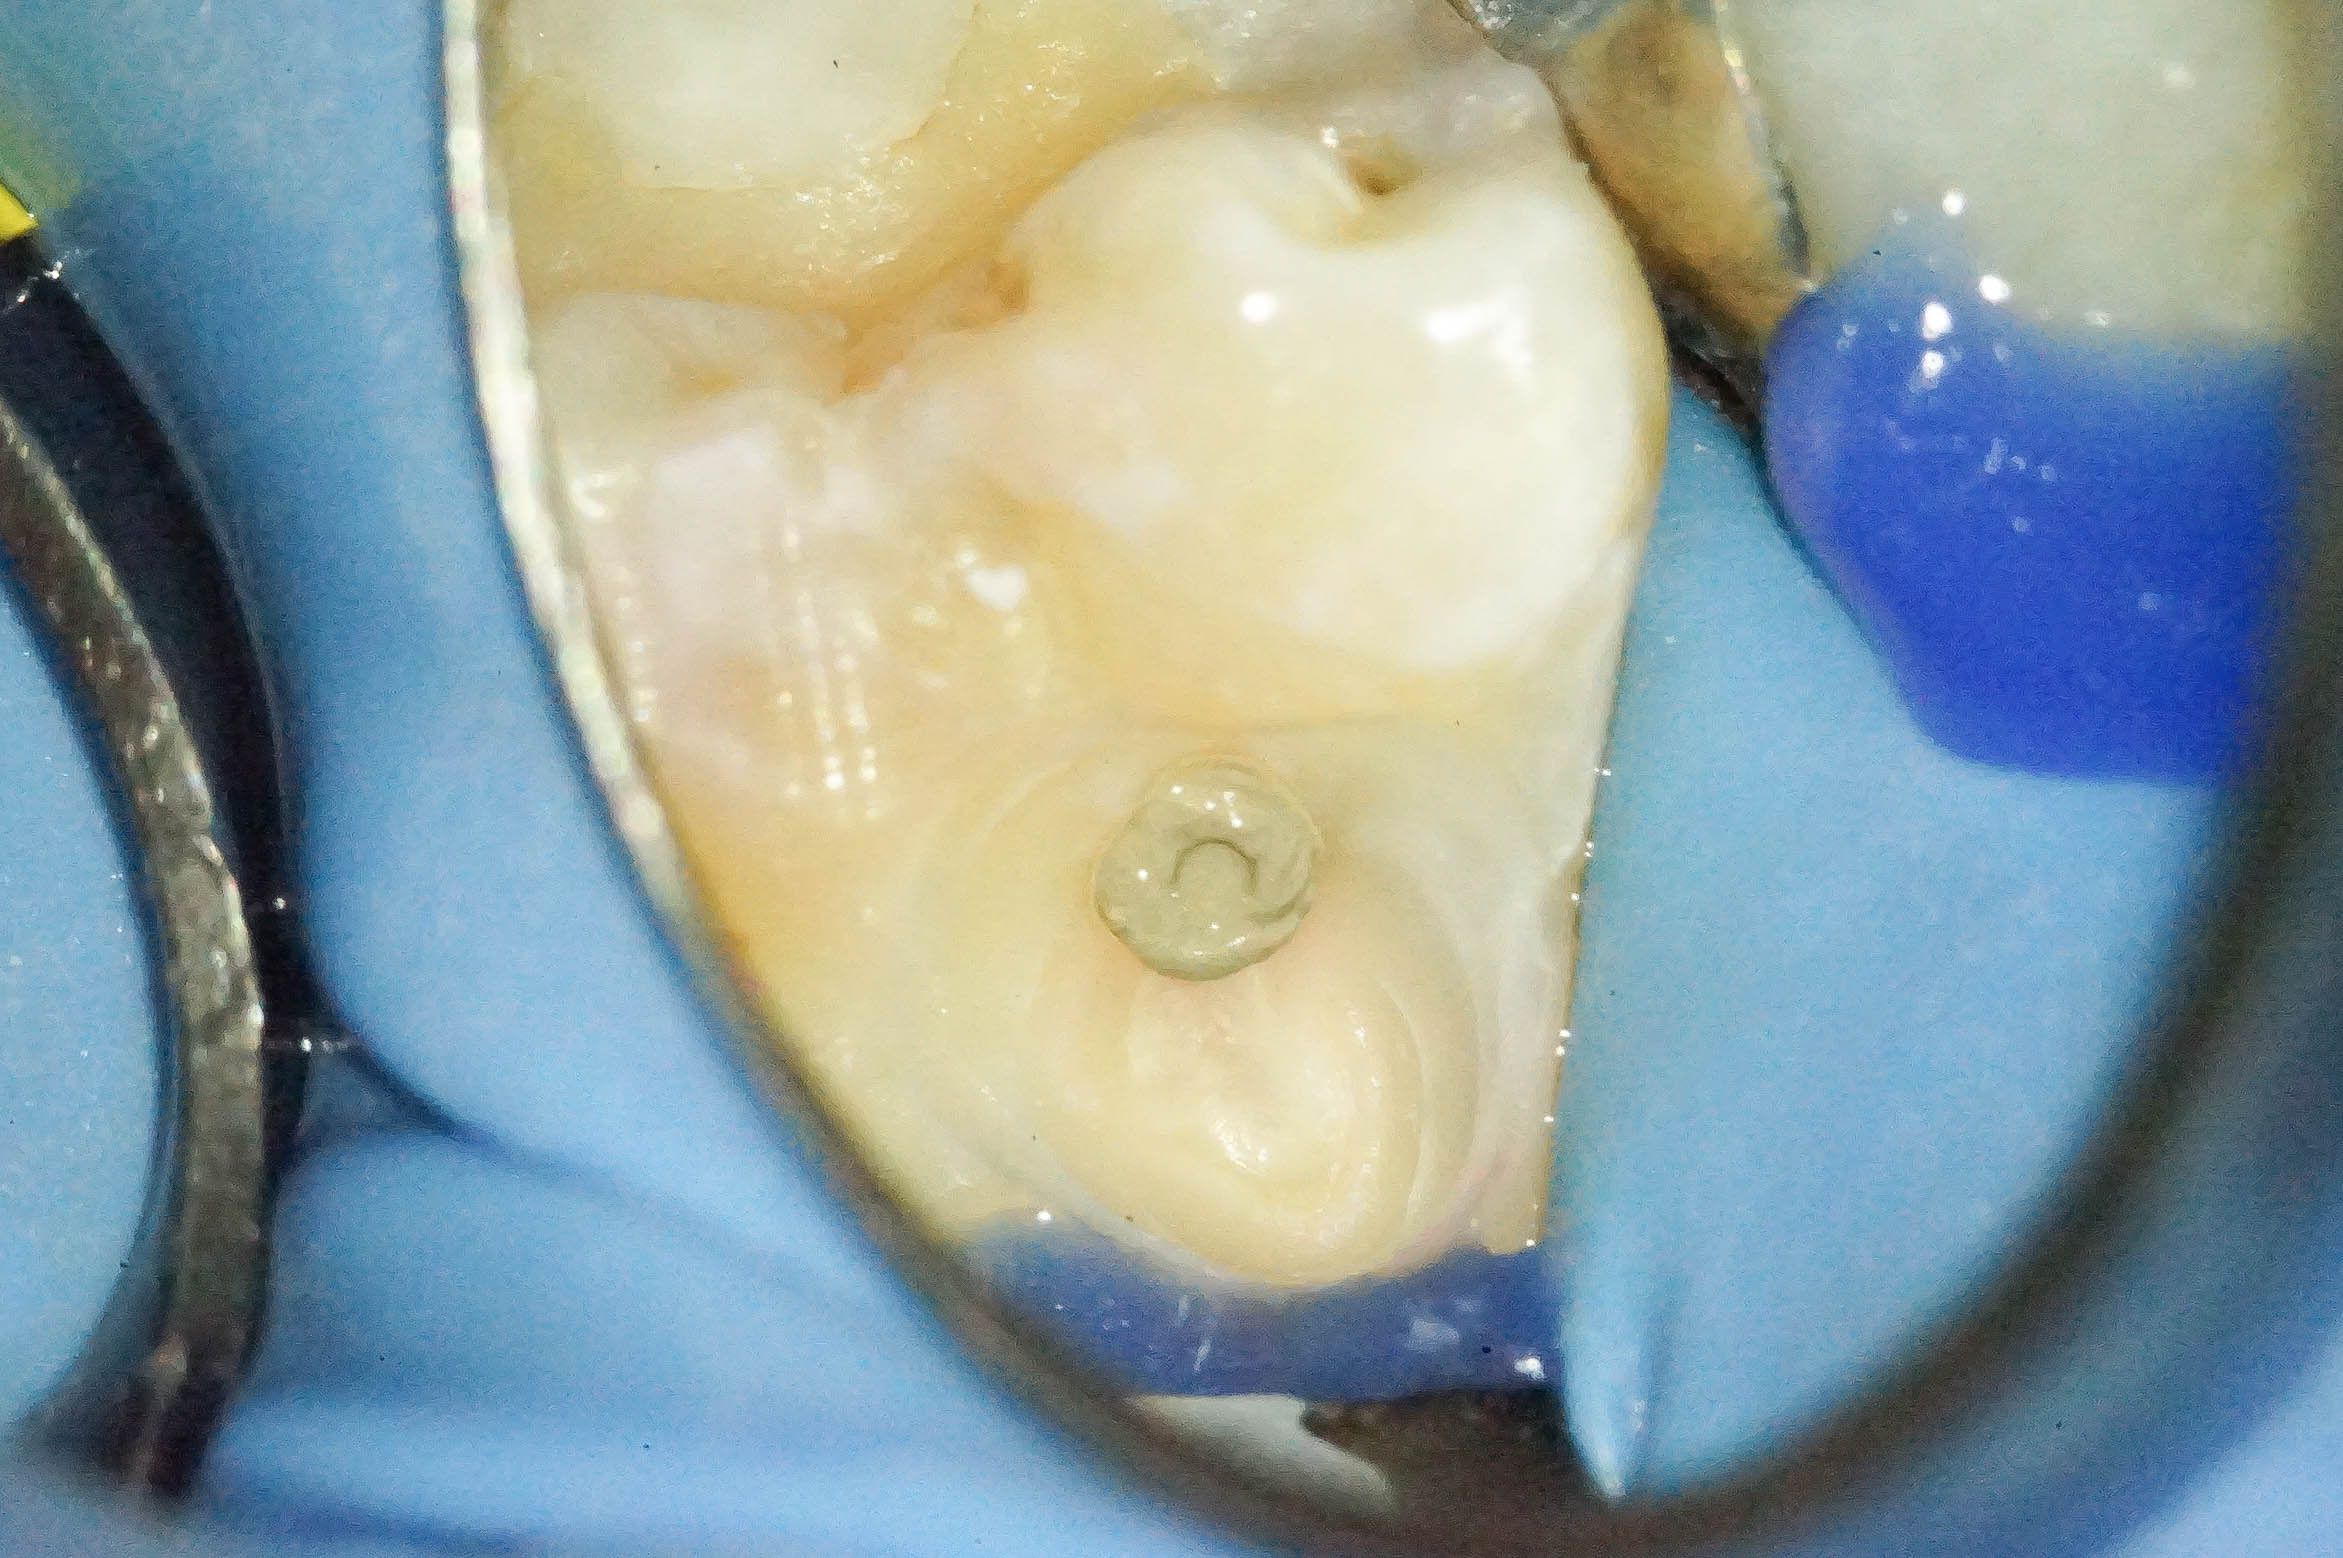

歯肉縁下ダイレクトボンディングを行った症例治療方法02

拡大して見てみると歯と歯肉の境目に齲蝕を認めます。

いわゆる普通の、保険治療でよく見かけるコンポジットレジンのその後 ですね。

治療直後はなにもトラブルが起きていませんが、数年後にトラブルが起き始める典型的な例です。